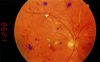

Proliferative Diabetic Retinopathy

White arrows → increased vascularity around the optic disk

Solid green overlays → cotton wool spots

Hatched Green Overlay → hard exudates

White Arrowheads → intraretinal hemorrhages

Red Arrowhead → microaneurysm

Proliferative Diabetic Retinopathy

Arrowhead → neovascularization

Blue overlay → microaneurysm

Green ovarlay → retinal hemorrhages hard exudates

Yellow overlay → venous beading

Proliferative Diabetic Retinopathy

White line overlay → neovascularization

Green overlay → fibrovascular proliferation around the optic disc

Red ovarlay → hard exudates

Hatched overlay → retinal hemorrhages

White arrowheads → scarring from previous laser photocoagulation

Nonproliferative Diabetic Retinopathy

(Hard exudates (well-demarcated yellow areas) and small intraretinal hemorrhages (red blotches) can be seen throughout the retina)

Neovascularization in Diabetic Retinopathy.